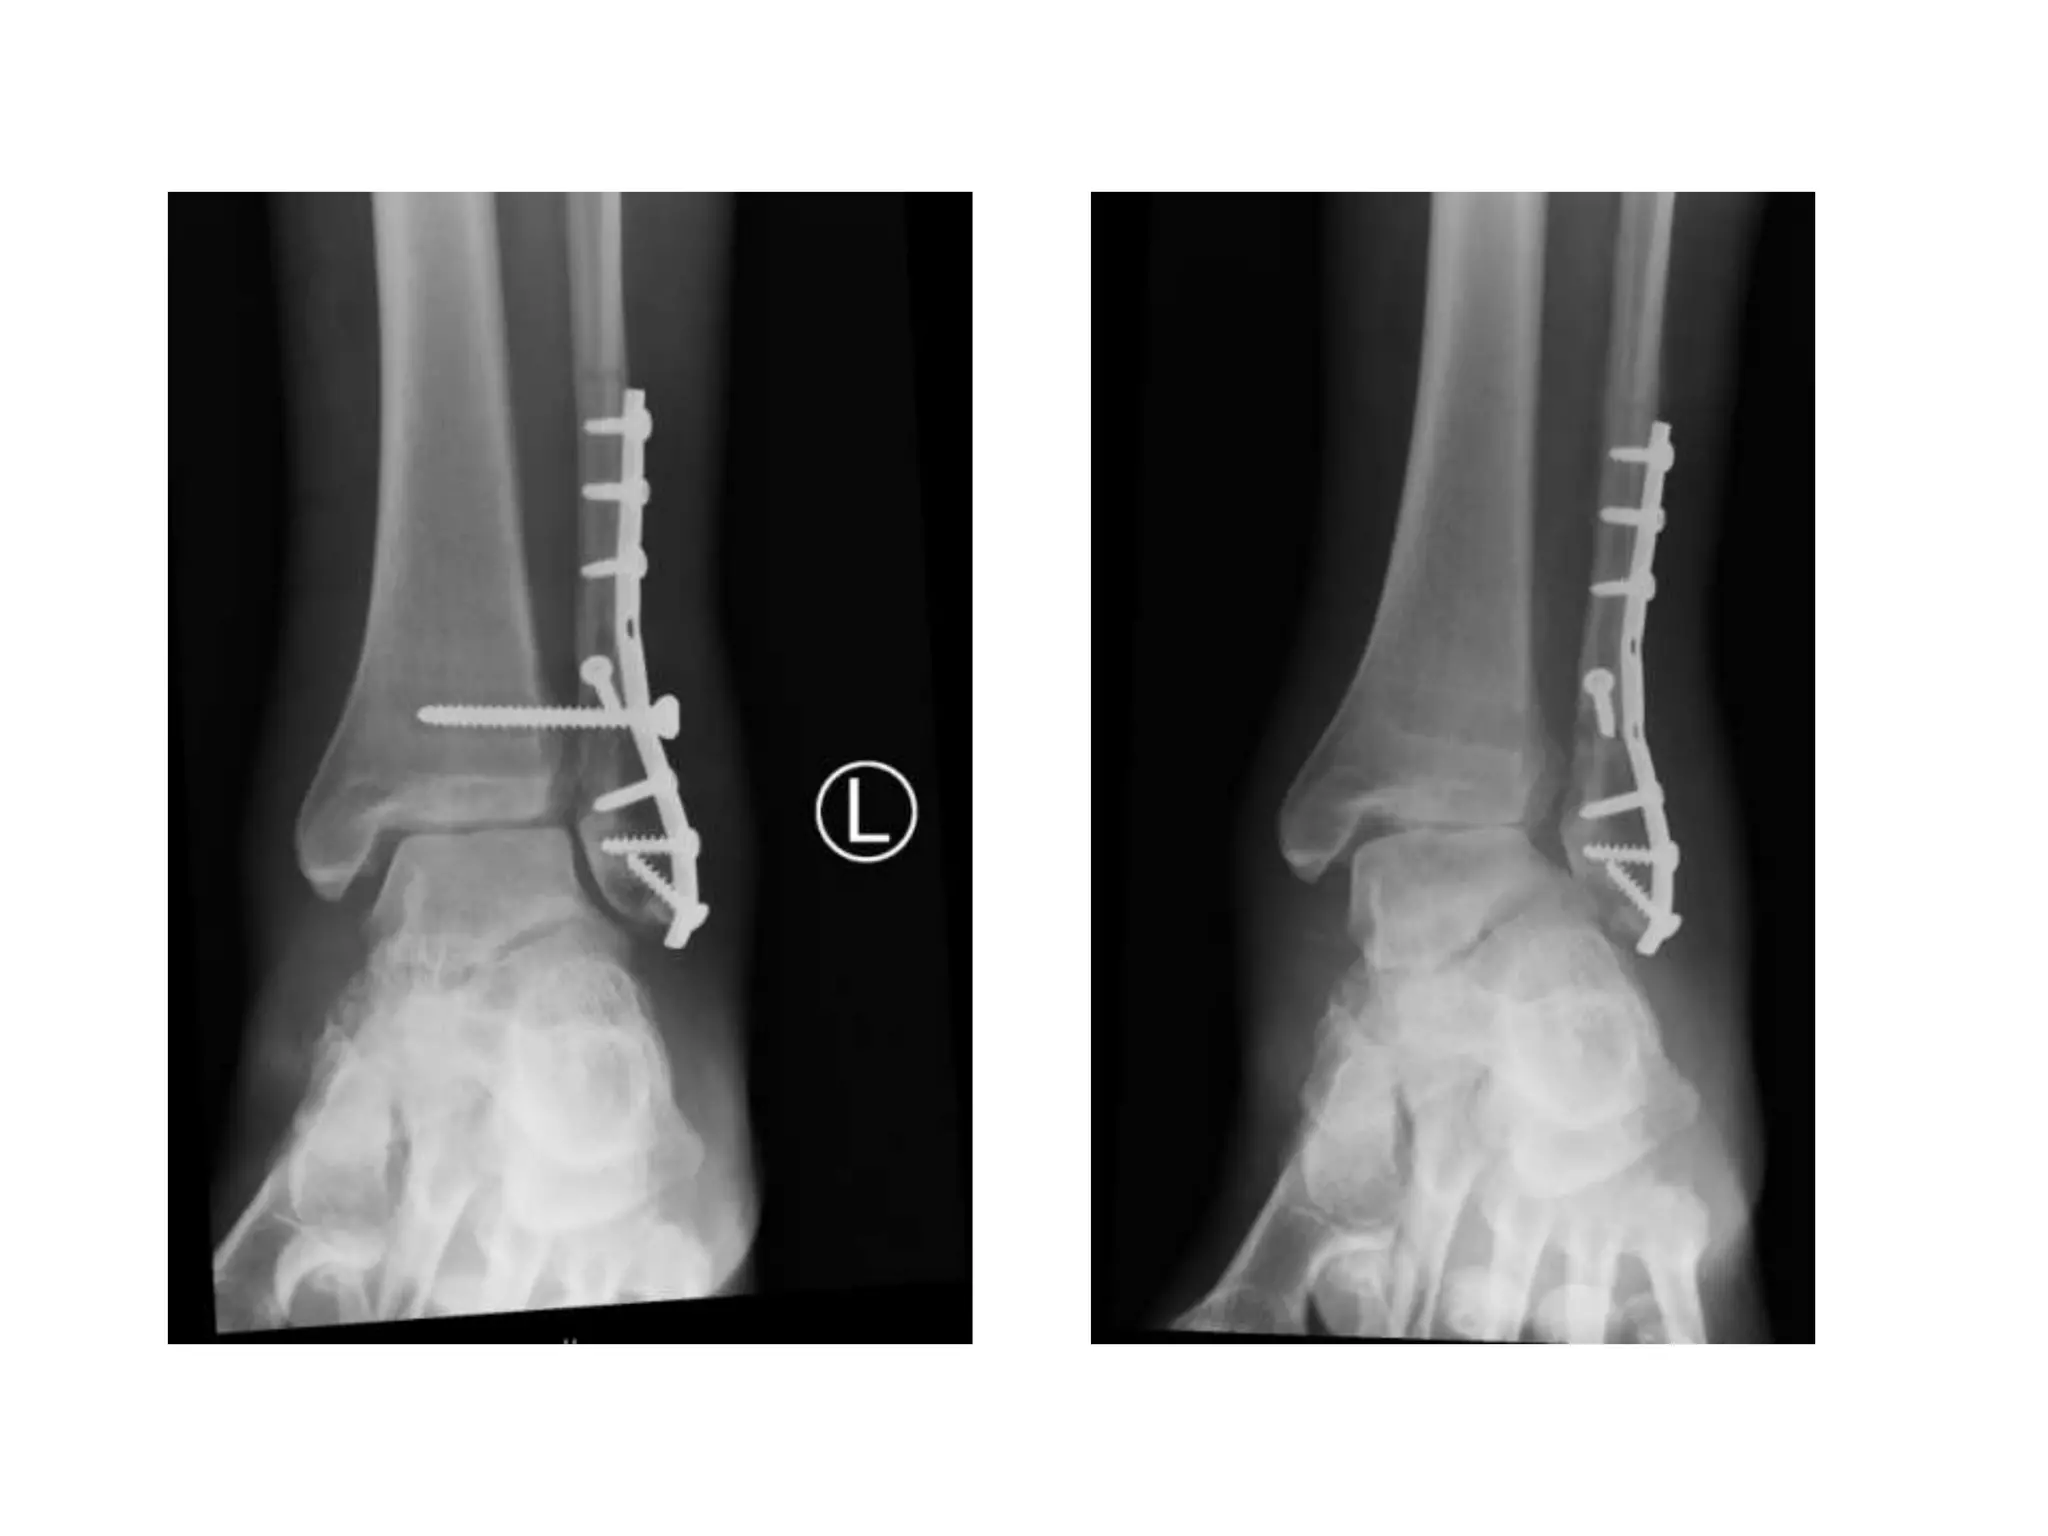

• Isolated Medial Malleolar

• Isolated Lateral Malleolar

• Isolated Posterior Malleolar

• Bimalleolar

• Trimalleolar

• Syndesmotic Injuries

• Dislocations

• Plafond/pilon

Ankle Fractures

• Unimalleoli: 70%

• Bilmalleolar: 20%

• Trimalleolar: 7%

• Open: 3%

Incidence

• Cast if undisplaced with no talar shift

• Fix if displaced

• Check the knee x-ray

Isolated Medial

Lateral

Type A: Fracture of the fibula below the level

of the syndesmosis

Type B: Fracture of the fibula at the level of the

syndesmosis

Type C: Fracture of the fibula above the level

Affects joint in all planes

Interosseous disruption

Often associated with posterior fracture

• Below the level of syndesmosis

• Generally treat in plaster or CAM 6/52 FWB

Weber A

• At the level of syndesmosis

• ORIF if any talar shift or displacement >2mm

• ORIF is medial structures not intact (functional

bimalleolar fracture)

• Lag screw fixation with neutralising plate

Weber B

Bimalleolar

Fracture Dislocation

• Principles in Management

– Early reduction and stabilisation

– Cast / ex-fix or ORIF if swelling appropriate

(usually <6hours or >6 days)